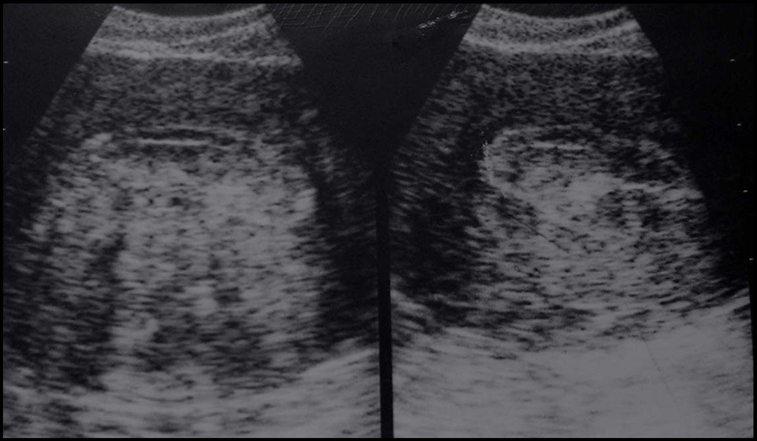

Cancer de l’endomètre. Bourgeons hyperéchogènes dans le muscle